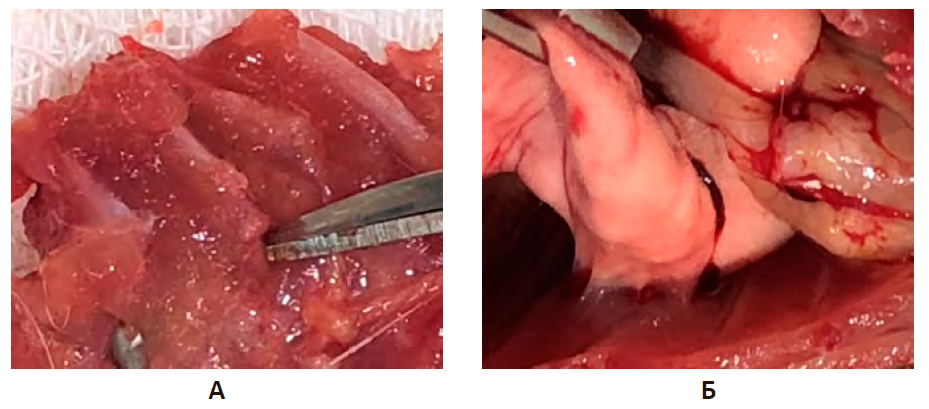

В результате проведенного исследования установлены достоверные различия в морфогенезе остаточных полостей у животных групп сравнения и опытных групп. При проведении сравнительной характеристики экспериментальной хронической эмпиемы плевры и спаечного процесса в плевральной полости без лечения и при различных способах биологической стимуляции спайкообразования было установлено, что на 10-е сутки эксперимента во всех группах исследования, в том числе в группе негативного контроля, в группе сравнения и в трех экспериментальных группах, макроскопически сохранялась остаточная полость. Выраженность спаечного процесса зависела от тактики ведения остаточной плевральной полости, возникшей при экспериментальном моделировании эмпиемы плевры.

В группе НКэп объем остаточной плевральной полости был максимальным и в среднем составлял 25,1±3,1 мм3. В основном у животных данной группы определялись единичные спайки (50,0%), в 36,7% случаев спайки отсутствовали, множественные спайки обнаружены лишь в 13,3%, при этом морфологически определялись преимущественно паутинные спайки. Полость была заполнена жидким гноем без признаков организации. Висцеральная плевра утолщена до 1–1,5 мм, в ее толще определялись абсцессы диаметром от 1 до 3 мм (рис. 8А).

В ГСэп также как и в группе НКэп тотальное заращение остаточной полости не наблюдалось. Однако определялись внутриплевральные спайки, как единичные – в 56,7%, так и множественные – 23,3%. Объем остаточной плевральной полости был меньше, чем в группе НК – 23,2±2,5 мм3, (p>0,05). В ГС остаточная полость эмпиемы была сформирована париетальной плеврой, висцеральной плеврой верхней доли, междолевой бороздой, нижней долей и диафрагмой. В толще плевры определялись множественные инкапсулированные абсцессы до 3 мм в диаметре. На поверхности плевры имелись очаговые отложения фибрина (рис. 8Б).

В опытной группе на фоне введения плазмы, обогащенной тромбоцитами, на 10-е сутки экспериментальной ЭП определялись остаточные полости небольшого объема, раздробленные единичными органными спайками на сектора. Внутриплевральные сращения чаще всего располагались в области реберно-диафрагмального синуса и были пронизаны вновь образованными сосудами, что свидетельствовало об активном формировании спаек (рис. 8В).

Рисунок 8 – Плевральная полость на 10 сут экспериментальной эмпиемы плевры в группе сравнения

Примечание: А. Группа негативного контроля (НКэп). Полость заполнена жидким гноем, множественные абсцессы. Б. Группа сравнения (ГСэп). В. Опытная группа (PRPэп).

На 20-е сутки экспериментальной ЭП в группе НК определялась остаточная полость, содержащая гнойный экссудат. Пиогенная оболочка была утолщена за счет отложения фибрина до 2 мм, инфильтрирована многочисленными микроабсцессами. Купол диафрагмы сглажен, отмечалась деформация синусов, при этом внутриплевральные сращения отсутствовали (рис. 9А).

В передненижних отделах плевральной полости у крыс ГСэп определялась остаточная полость эмпиемы с утолщенными стенками, содержащая организованный экссудат. Обнаружены многочисленные спайки, преимущественно пленчатые и плоскостные, локализованные в плевро-диафрагмальных синусах и междолевой борозде. Выраженный внутриспаечный воспалительный процесс и богатая неоваскуляризация свидетельствовали об активном формировании спайки (рис. 9Б).

При биологическом потенцировании адгезиогенеза с помощью введения плазмы, обогащенной тромбоцитами, определялись деформированные (за счет спаечного процесса) остаточные полости без гнойного содержимого, с очаговыми отложениями фибрина на стенках, толщиной до 2 мм. Морфологически спайки были представлены широким спектром: единичные органные спайки сочетались с множественными пленчатыми и лентовидными сращениями, которые хаотично располагались внутри остаточной полости значительно сокращая ее объем (рис. 9В).

Рисунок 9 – Плевральная полость на 20-е сутки экспериментальной эмпиемы плевры

К окончанию эксперимента (30-е сутки) во всех группах регистрировались случаи ликвидации остаточных полостей, однако в группе НКэп полость эмпиемы определялась достоверно чаще, чем в группе сравнения и в опытной PRPэп группе (р<0,05). При этом в НКэп объем остаточной полости был наибольшим (19,3±1,7 мм3). Отмечалось утолщение париетальной и висцеральной плевры, с субплеврально расположенными абсцессами. У животных данной группы превалировали единичные спайки (50,0%), в 30,0% случаев спайки отсутствовали, множественные спайки обнаружены лишь в 13,3%, тотальное заращение зарегистрировано лишь в 6,6% (рис. 10А).

При введении доксициклина (ГСэп) объем остаточной полости эмпиемы в среднем составлял 16,5±1,5 мм3, заращение остаточной полости обнаружено в 13,3%, в 16,7% определялись единичные спайки, в 46,7% – множественные. Спайки были представлены зрелыми массивными швартами, расположенными в нижних отделах (рис. 10Б).

В опытной группе (PRPэп) на 30-е сутки тотальное заращение полости эмпиемы зарегистрировано в 13,3%. Объем остаточной плевральной полости в среднем составил 12,1±0,8 мм3. Отсутствие спаек зарегистрировано в 20,0%. Морфологически определялись лентовидные и плоскостные спайки (рис. 10В).

Рисунок 10 – Плевральная полость на 30-е сутки экспериментальной эмпиемы плевры

Примечание: А. Группа негативного контроля (НКэп). Б. Группа сравнения (ГСэп). В. Опытная группа (PRPэп).